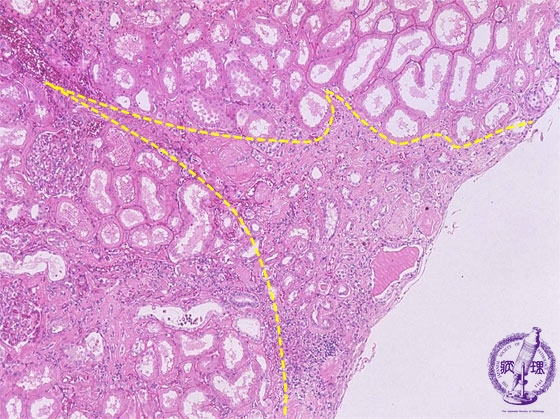

- ★(10)Nephrosclerosis(benign nephrosclerosis)

Microscopic image (HE, mid-power): The cortex shows wedge-shaped atrophy (yellow dotted line) with scar and a mononuclear cell infiltrate.